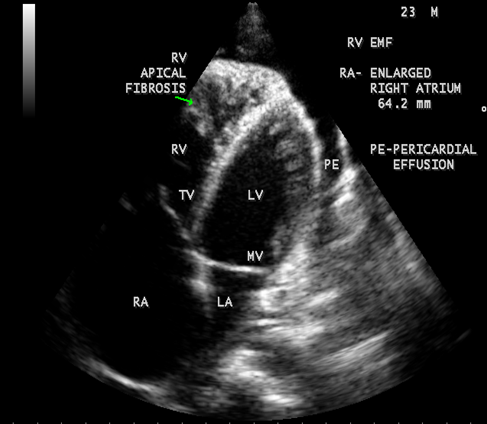

Case 2 (Right ventricular endomyocardial fibrosis in Tuberculosis) A 23-year old male was admitted with sudden onset of ascites for one-month duration. He was treated for pulmonary tuberculosis 3 years back with a positive sputum AFB (acid fast bacilli). Blood chemistry revealed as ( Total count-7400 cells/cu.mm of blood ( normal-4000 to 11000 cells/cu.mm of blood), polymorphs -70% (normal- 40 to 75 %), lymphocytes-22%(normal-20 to 40%), eosinophils-8% (normal- 1 to 4%), ESR (erythrocyte sedimentation rate)-10 to 22 mm/hour ( normal- 0 to 15mm/hour), platelets-2.5 lakhs/cu.mm of blood and a mild elevation of serum bilirubin-total-2mg/dl(normal---up to 1.2 mg/dl) direct-1.2mg%(normal—upto—0.3 mg/dl), indirect-0.8mg%(normal – upto 0.9 mg/dl). Total serum proteins 5.2gm% (normal -6.6 to 8.3 gm/dl), albumin-3.2gm% (normal- 3.5 to 5.0 gm/dl), globulin -2.0gm%(normal 2.5 to 3.5 gm/dl ), urea-39 mg%(normal 15-50 mg/dl), creatinine-0.1mg%(normal- 0.7 to 1.4mg/dl), sugar-112 mg/dl random (normal – 80 to120 mg/dl- random sample). Ascites fluid tapping revealed an exudate (protein-3 gm%) and cytology revealed no malignant cells. Ascites fluid adenosine deaminase (ADA)activity revealed 10.4 U/L (normal < 40>Figure 8. His pulse rate was 108 bpm and blood pressure 100/70 mmHg. Auscultation revealed clear lung fields and no cardiac abnormalities. ECG revealed no arrhythmias and X-ray chest showed right- sided pleural effusion and extensive calcification over the cardiac shadow as shown in Figure 9. Transthoracic echocardiography revealed apical fibrosis of right ventricle, moderate pericardial effusion, right atrial dilatation as shown in Figures 10 and 11, suggesting right ventricular endomyocardial fibrosis and severe tricuspid regurgitation as in Figure 12 indicates coexisting pulmonary hypertension due to pulmonary damage caused by tuberculosis as shown in Figure 13 and free RV outflow tract as in Figure 15. Patient was treated with antituberculous drugs, antifailure measures such as digoxin and diuretics, ascites fluid tapping and antibiotics. He showed mild improvement in his symptoms.

Figure 11: Apical four chamber view suggesting RV (right ventricular) apical fibrosis, RA dilatation and severe tricuspid regurgitation suggesting right ventricular endomyocardial fibrosis with an extension of fibrosis in the LV apex

Figure 12: Apical four chamber view showing the RV apical fibrosis with mild pericardial effusion in a 23-year old male with tuberculosis.